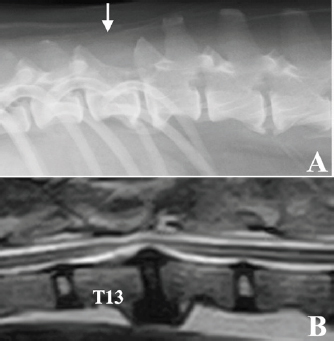

After treatment, the dog lived for approximately 10 years with mild proprioceptive deficits in the left hind limb. No tumor recurrence was observed on periodic follow-up magnetic resonance imaging (MRI) examinations carried out 10 and 21 months after surgery. Nine years after surgery, the dog returned to the hospital to evaluate the thoracolumbar spinal cord due to the gradual development of hindlimb weakness. Plain radiography of the thoracolumbar spine showed spondylosis deformans between T13–L1 and L2–3, with the former being consistent with the surgical site (Fig. 3A). MRI examination showed no recurrent tumor tissue in the thoracolumbar spinal cord; however, there was slight compression of the spinal cord from the ventral side at T13–L1 (Fig. 3B). This was thought to be due to the proliferation of bony tissues associated with intervertebral instability after laminectomy. The dog died 11 years after surgery for reasons unrelated to the tumor. According to the owner, the dog had vomiting of unknown cause for several months and died of aspiration pneumonia. No necropsy was performed.

Fig. 3. Radiographic and MRI findings of the thoracolumbar spine of the case 9 years after surgery. (A) Radiographic features of spondylosis deformans were observed in both T13–L1 and L2–3. The spinous process of T13 was missing due to laminectomy (white arrow). (B) MRI (T2-weighted image) showed that the spinal cord was slightly compressed from the ventral side in T13–L1, probably due to the proliferation of bone tissue due to spinal instability. No tumor tissue was observed in the spinal cord.